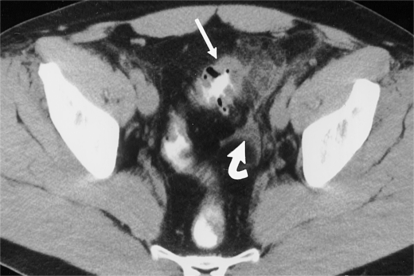

乙状结肠CT图片

与乙状结肠相关的疾病:

1、乙状结肠冗长症:又称先天性长结肠,是指乙状结肠的长度超过正常范围并伴发慢性便秘,或腹痛、腹胀等症状的一种疾病。

2、乙状结肠癌:是发生在乙状结肠的恶性肿瘤,属于结肠癌的一种。乙状结肠癌的具体病因尚不明确,可能与饮食、慢性炎症、遗传因素、癌前病变等因素有关。